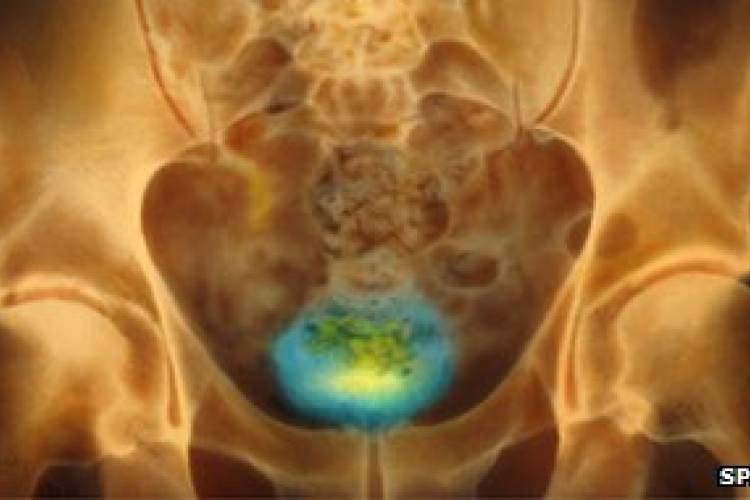

Gerinssérülteknek segíthet a hólyag irányításában egy új készülék

Brit kutatók kifejlesztettek egy készüléket, amely gerincsérülteknek segíthet a hólyag irányításában.